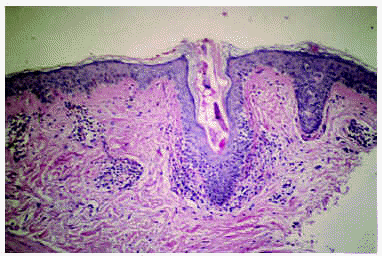

Se realizó biopsia de una de las lesiones, cuyo estudio histopatológico mostró una epidermis de espesor irregular con aplanamiento de las crestas interpapilares y discreto aumento de pigmentación de la basal. Se observaba, además, dilatación de los infundíbulos pilosos que contenían queratina y regular cantidad de parásitos tipo Demodex folliculorum (fig. 2). En la dermis había discreto edema, dilatación capilar y moderado infiltrado inflamatorio mononuclear linfohistiocitario de predominio perivascular y perianexial con compromiso focal de anexos pilosos.ç

Fig. 2.--Dilatación folicular con presencia de ácaro de Demodex folliculorum y reacción inflamatoria perifolicular.